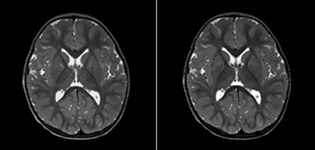

pCASL helps assess brain perfusion without contrast

Pseudo-continuous arterial spin labeling (pCASL) was developed for brain perfusion imaging without contrast agent. “This is very desirable in pediatric patients where the general trend is to limit the administration of contrast,” says Dr. Miller.

Dr. Miller uses pCASL for all patients who present with chronic and acute cerebrovascular abnormalities such as acute stroke, as well as patients who present with signs of acute inflammation in the brain, and occasionally in patients with tumors, to assess the perfusion status of their tumor.

“In combination with diffusion weighted imaging, it can help give a more extended assessment of the degree of perfusion abnormality in a patient who is suffering acute ischemia. We have a number of patients who have chronic arterial insufficiency due to prior arterial abnormalities or acquired arterial abnormalities such as sickle cell disease or neurofibromatosis. Sometimes the child’s first manifestation of disease progression is a reduction in brain perfusion before stroke symptoms manifest clinically or in diffusion weighted imaging. We use pCASL to help delineate the perfusion abnormality.”